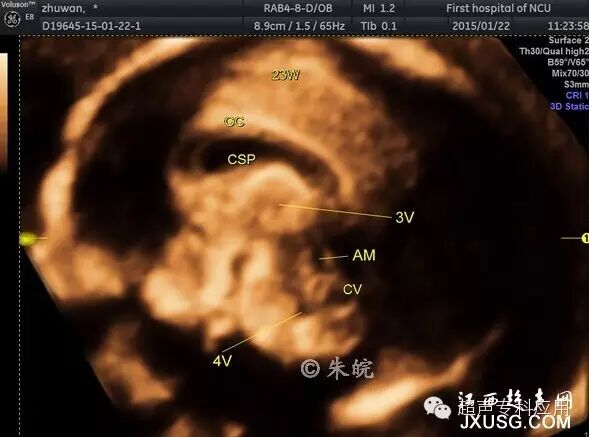

1.3 三维重建颅脑正中矢状平面 由于胎儿在官内的位置,二维超声往往只能获取颅脑横断面。颅脑畸形的超声筛查通过胎头横断面扫查即可完成,但对某些横断面上出现的异常改变或怀疑颅脑中线结构异常,则需要在颅脑矢状平面上进行诊断。胼胝体缺失、Dandy-walker综合征是较为常见的中枢神经系统异常,临床上常常需要明确诊断或进行鉴别诊断,若不进行颅脑矢状平面的扫查,有时会给诊断带来困难。三维重建颅脑正中矢状平面能够显示透明隔、胼胝体、第三脑室、第四脑室及小脑蚓部、后颅窝等中线结构,测量小脑蚓部径线,这是二维超声难以达到的。有文献报道显示,与二维超声相比,利用三维超声诊断颅脑异常的敏感性从二维的82.7%提高到三维的93%。

胎儿正中矢状切面三维重建:

CC:胼胝体 CV:小脑蚓部 CSP:透明隔腔 3V4V:第三脑室第四脑室 AM:中脑水管

胎儿正中矢状切面三维容积对比成像